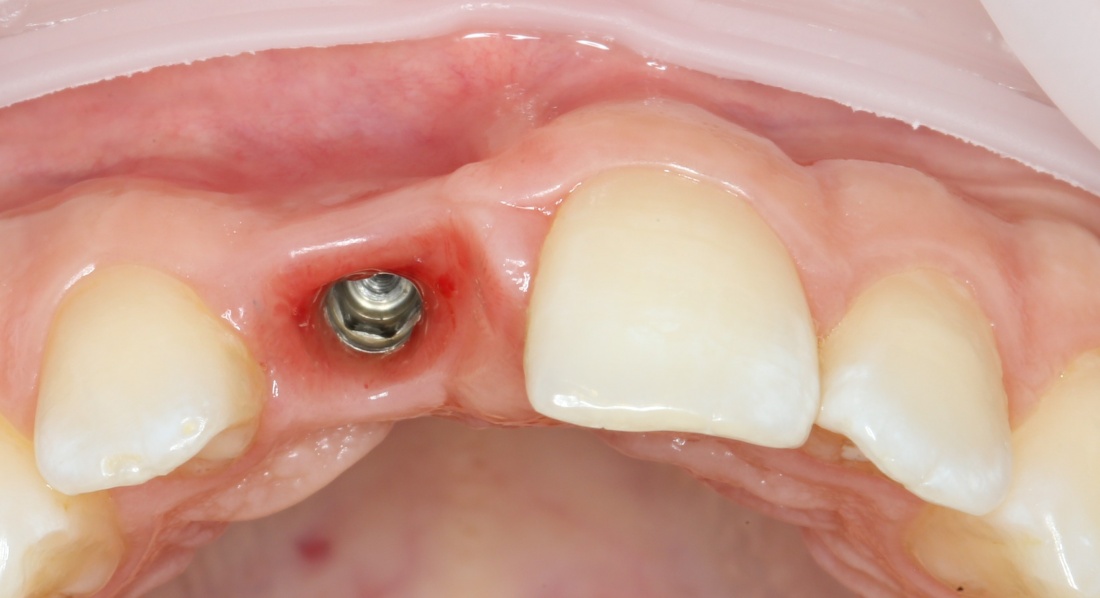

Через неделю можно снять швы. Область раны выглядит следующим образом:

А через два месяца — вот так:

На этом этапе, для создания более правильного десневого контура, можно поменять формирователь размер больше: